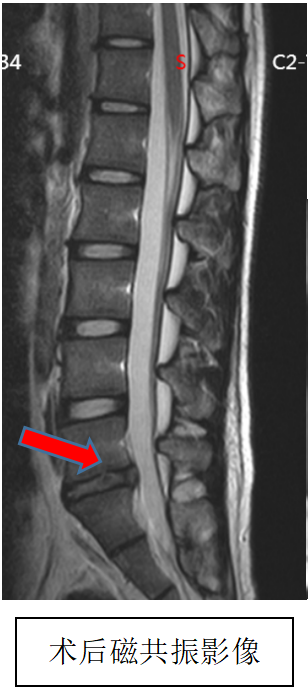

吴静晔主任是成人ai 派驻郑州医院的脊柱外科专家,也是成人ai 脊柱外科的执行主任,在为小明做了全面检查后,结合术前 MRI 精准定位病变部位,在充分沟通诊疗方案与风险后,为小明实施了微创手术,精准解除神经压迫。

术后即刻复查磁共振显示,手术达到预期效果,小明的疼痛快速缓解,麻木感逐渐消退,终于能正常坐立、平稳走路。